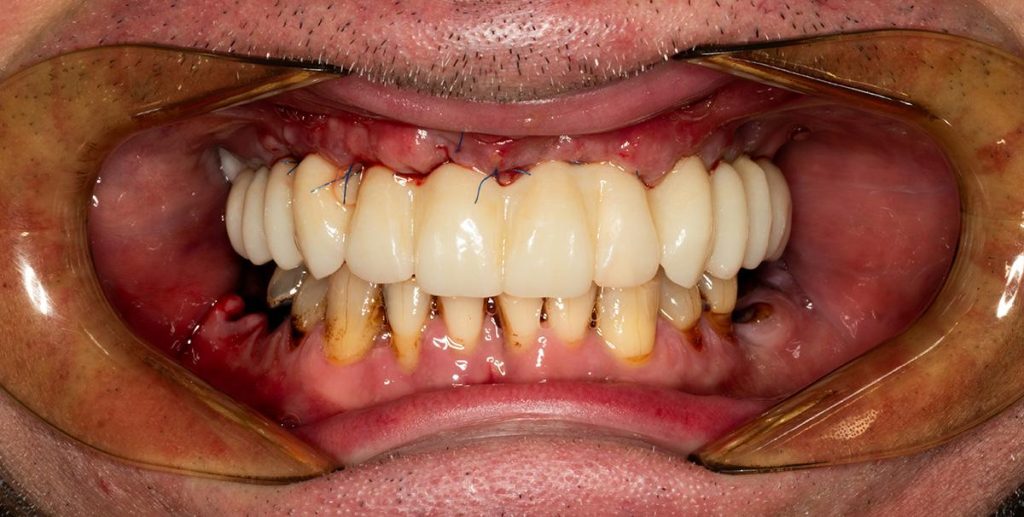

Przeprowadziliśmy precyzyjne leczenie implantologiczne, wszczepiając 11 implantów w szczęce i żuchwie. Konieczna była też regeneracja kości. Po 6 miesiącach gojenia nastąpiła odbudowa pełnołukowa. Kształt, kolor i ustawienie zębów zostały dobrane oraz wykonane na indywidualne życzenie Pacjenta.

Leczenie chirurgiczne i implanto-protetyczne przeprowadził lek.stom. Michał Badowski.